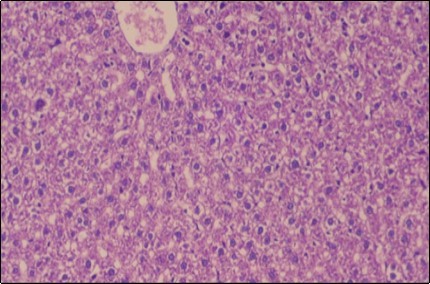

Effect of Ator, Fennel and Their Combination on the Histology of the kidney of the Obese Rats

The histological examination of the kidney of the control rats fed on a standard diet showing normal rounded capsules with normal Bowman's glomeruli, round proximal tubules and elongated distal tubules with high cuboidal cells figure 1. The rats fed (HFD) showed fatty degeneration of the tubules with eosinophilic material deposition, glomerular atrophy with wide urinary space and distal tubules with extrusion of nuclei into lumen figure 2. By comparison kidneys of rats which were treated by fennel after being obese and the control rats observed partial improvement in both Bowman's capsules and proximal tubules. Note the distal tubules show less focal fatty infiltration figure 3.While examination of rats kidney that were treated by ator after obesity showed improvement in Bowman's capsules with normal glomerular and partial improvement in proximal tubules and distal tubules, figure 4. Kidney of rats that were treated by fennel and ator after obesity and the control rats showed high improvement in the tissues with normal glomerular and that Most of Bowman's capsules and renal tubules, restoring their normal appearance figure 5.

Figure 1.Photomicrogragh of kidney section of control rat showing normal rounded capsules with normal Bowman,s glomeruli, round proximal tubules and elongated distal tubules with high cuboidal cells , (H&E) (40X).

Photomicrogragh of  kidney section of          control rat showing normal rounded capsules with normal Bowman,s glomeruli, round proximal tubules  and elongated   distal tubules with high cuboidal cells , (H&E) (40X).